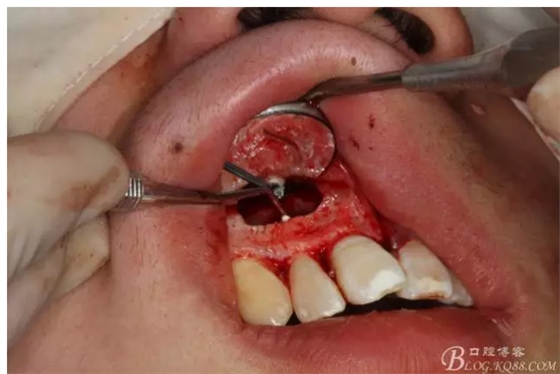

圖3.依缺損部位為中心,逐漸去骨,完整暴露出囊壁。

圖4.摘除囊壁后形成的巨大骨腔